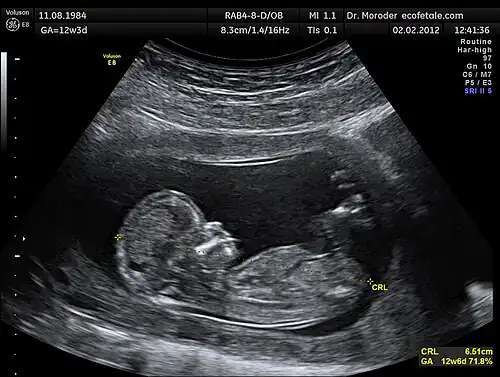

Modern ultrasonography use arrays of small transducers, each of which are individually electronically controlled to achieve an effect know as beamforming. When using this technique, control of the phase relation between array elements results in control over the emitted beam's direction and focal depth.[7] To produce a two-dimensional ultrasound image, the ultrasound beam focal position is swept through a region, and the recorded reflected waves are correlated to the particular focal locations. The exact process by which this general concept is accomplished varies with each ultrasonography instrument. Figure 1 provides a sample 2D image produced by the sweeping of the focal location through a 2D plane.

Figure 1: 2D Obstetric ultrasound image.